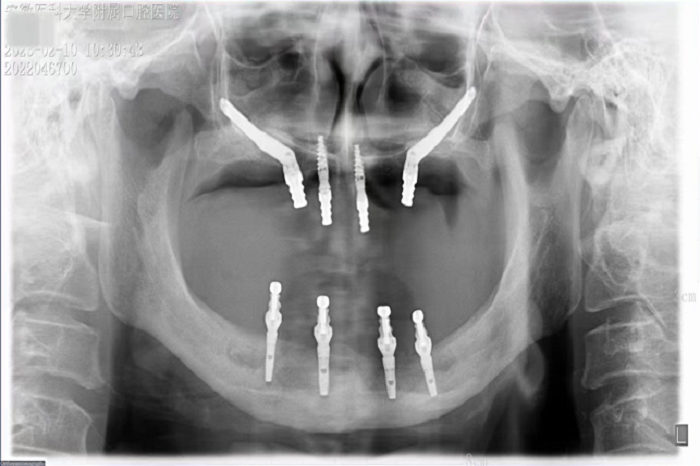

2月8日,DB电竞 种植科主任刘鑫带领其团队完成一例上颌骨“穿颧”、下颌神经游离种植手术。该手术是继2019年种植科完成首例穿颧种植术后的第二例穿颧种植。

据悉,患者潘女士54岁,由于重度牙周炎导致全口牙齿缺失,严重影响面容及咀嚼功能,因颌骨严重萎缩无法进行活动义齿修复,遂来DB电竞 种植科要求行上颌稳固的修复。通过检查发现潘女士上下颌骨骨量严重不足,经反复比对和考量,刘鑫主任制定了对患者上颌骨进行穿颧种植修复、下颌骨通过神经游离进行种植的方案。经过患者与家属深思熟虑后,接受了行穿颧种植术的建议。治疗组通过专业三维设计软件规划植体,口腔颌面外科和种植科专家共同完成了穿颧种植手术。患者术后第一天情况良好,无明显肿胀,精神状态佳。